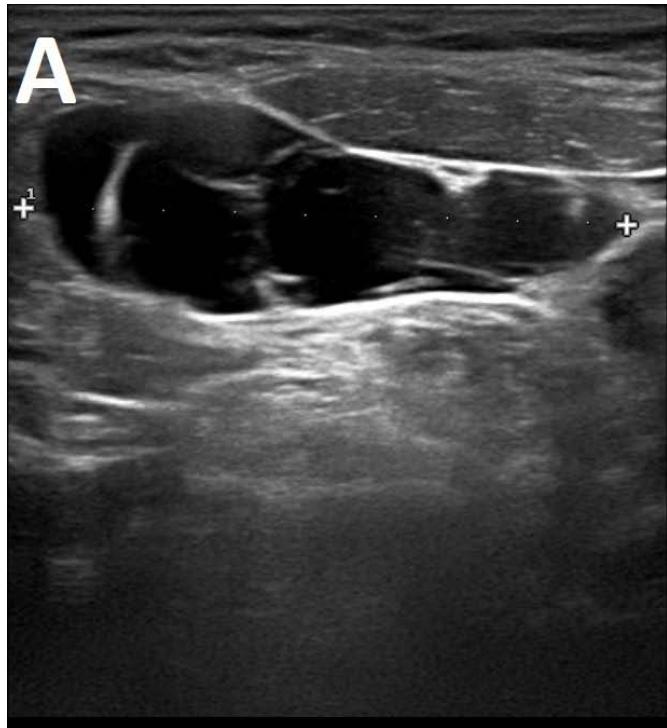

Figure/Patient 1

A 7 year-old girl presenting with a tumefaction at the level of the right latero-cervical region. US scans show a $43 \times 14$ mm subcutaneous fluid formation with septa extending from the root of the neck to the submandibular region (A-B). Doppler-mode demonstrates lack of blood flow within the lesion or the septa (C-D). Diagnosis of cystic lymphangioma is done.